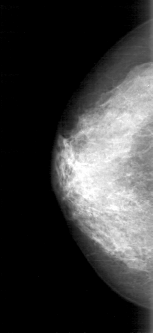

D_4158_1.RIGHT_MLO

RIGHT_CC LINES 4981 PIXELS_PER_LINE 2281 BITS_PER_PIXEL 12 RESOLUTION 43.5 NON_OVERLAY

RIGHT_MLO LINES 5281 PIXELS_PER_LINE 2176 BITS_PER_PIXEL 12 RESOLUTION 43.5 NON_OVERLAY